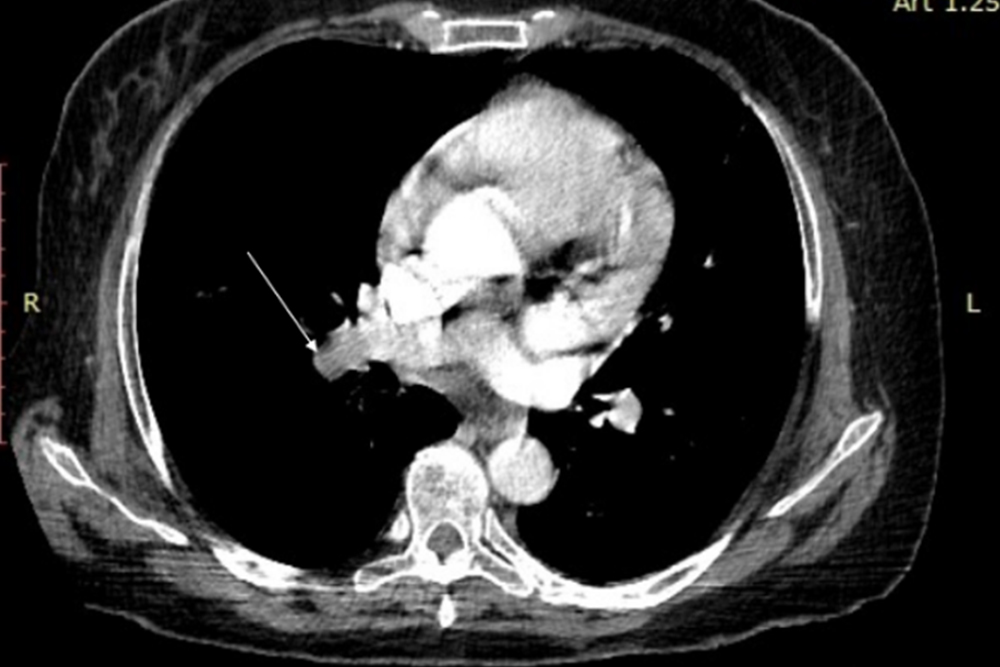

Учёные НИУ «БелГУ» совместно с коллегами из Первого Московского государственного медицинского университета им. И.М. Сеченова, Российской медицинской академии непрерывного профессионального образования и Российского университета дружбы народов изучили редкие клинические случаи сочетания тромбоэмболии легочной артерии и диффузного альвеолярного кровотечения. В результате плодотворного сотрудничества была разработана новая лечебная тактика в ситуации сочетания двух разнонаправленных по патофизиологическим итогам явлений – тромбоза и геморрагии.

По словам профессора кафедры семейной медицины, доктора медицинских наук Андрея Третьякова, тромбоэмболия (закупорка оторвавшимся тромбом) в бассейне легочной артерии (ТЭЛА) и диффузное альвеолярное кровотечение (ДАК) являются наиболее неблагоприятными, порой фатальными осложнениями ряда системных заболеваний сосудов и соединительной ткани, в том числе гранулематоза с полиангиитом и микроскопического полиангиита (прим.: системные васкулиты малых сосудов, с преимущественным поражением оториноларингологической зоны, дыхательной системы, сердца и почек). В особых случаях явления ТЭЛА и ДАК развиваются одновременно, что значительно утяжеляет состояние больного, затрудняет диагностику и лечение. При этом учёные отмечают недостаточную исследованность этой проблемы.

В результате анализа описанных в исследованиях клинических случаев, учёные пришли к выводу, что совместное присутствие данных осложнений системного васкулита, в зависимости от хронологии событий, допускает три клинических варианта сочетаний. Первый – отсроченный от ТЭЛА дебют ДАК; второй – совместное развитие ТЭЛА и ДАК и третий – опережающее ТЭЛА начало ДАК. Для каждого из сценариев медики подробно изложили конкретную программу терапии.